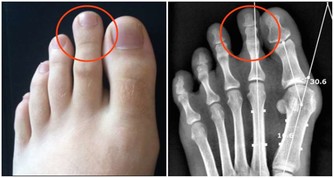

張大伯幾年前做了心臟支架手術,每天都要服用阿司匹林,就這樣吃了很長時間,他突然發現自己的腳趾關節疼痛難忍,還有點發紅,自己也沒犯飲食忌諱,怎麼痛風發作了呢?家人趕緊帶張大伯到醫院檢查。

醫生向張大伯解釋,阿司匹林會影響尿酸代謝,不適合痛風患者長期服用。

張大伯後悔不已,當初自己覺得痛風和心臟支架是兩碼事,就沒有告訴醫生自己患有痛風,沒想到栽在這件事上了。